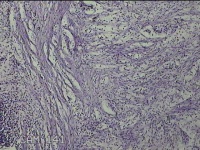

直肠息肉

性别

女

年龄

39岁

临床诊断

混合痔

一般病史

反复肛门肿物3月。

标本名称

大体所见

灰白暗红色条索状肿物5.3x2x0.8cm一个,表面糜烂,切面灰白暗红色,质软。

考虑内痔,伴出血、炎症。